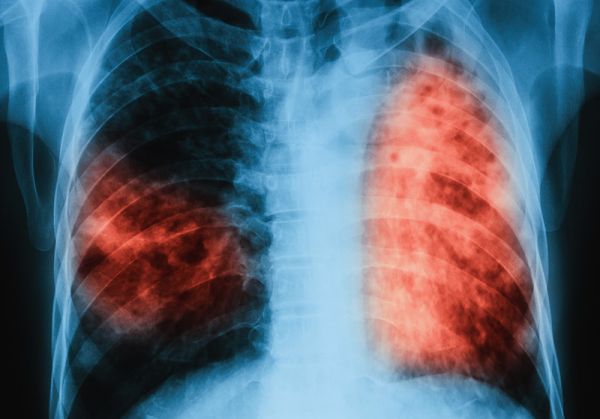

„Със средства на Глобалния фонд беше изградена специализирана електронна информационна система за регистриране на пациенти с туберкулоза, суспектни и контактни лица. Също така бяха изготвени хартиени и електронни образци на учетни форми на лечебните заведения за дейностите по контрола на туберкулоза, които ще продължат да бъдат използвани за отчитане и не се изисква допълнителен ресурс за разработването им. Медицинските специалистите от лечебните заведения са преминали обучение за запознаване с методическите указания по диагностика, лечение и контрол на туберкулоза и резистетна туберкулоза и работа с информационната система, попълване на данни в журналите за регистриране на случаи на туберкулоза, суспектни и контактни лица и лабораторни журнали“, пише още в доклада.

Наредбата е съобразена с Целите на устойчивото развитие на ООН, Глобалната стратегия на СЗО за спиране на туберкулозата, План за действие за борба с туберкулозата за Европейският регион на СЗО 2016-2020 на Регионалния комитет на СЗО за Европа, стратегията „Здраве 2020“, както и други международни стратегически документи и методически указания.